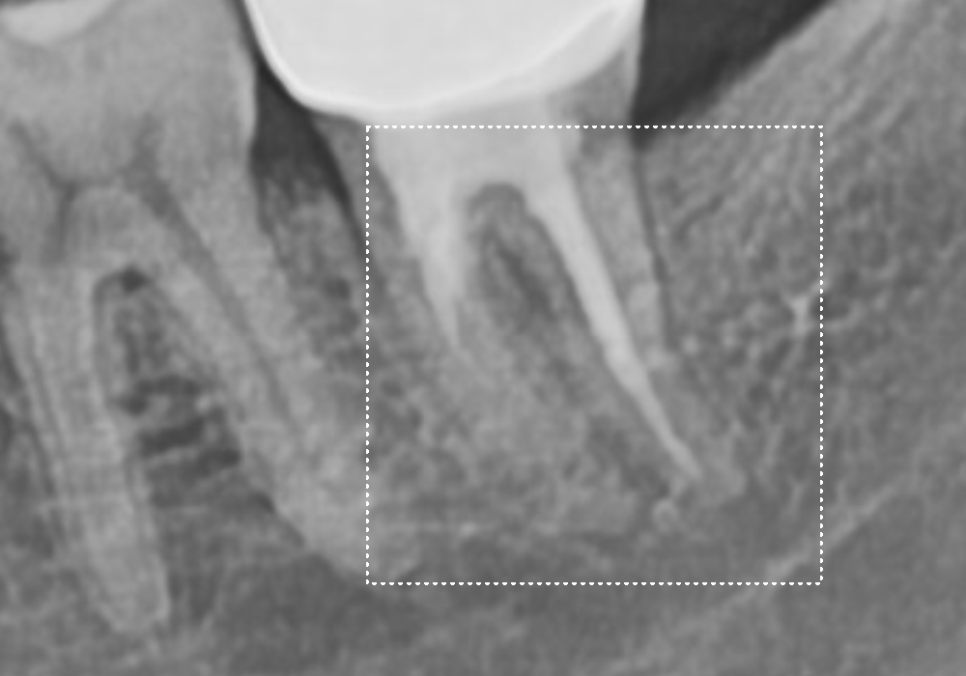

CT를 살펴볼게요~

241015

혹시 앞서 보여드렸던 환자와의

차이점을 눈치채셨나요?

빨간 동그라미로 표시한 하치조 신경인데요.

이 신경과 뿌리 끝 사이의 뼈가

확실히 뼈가 꽉 차 있고

하얗게 밀도가 높은 느낌이 들죠~?

이 환자분은 뿌리 끝에 염증이

있었던 게 아니라,

치아 자체가 약해 뿌리만 부러진 상태였기에

주변 뼈는 아주 건강하게 남아 있었습니다.

이렇게 토대가 튼튼하다면

치아를 뽑는 당일 임플란트를 바로 심을 수 있어요.